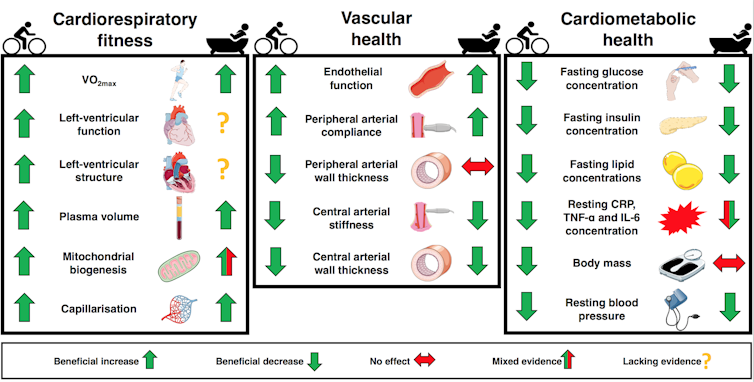

Notre récente revue de la littérature scientifique a révélé que se rendre au sauna ou prendre un bain chaud régulièrement peut avoir des effets bénéfiques sur la santé similaires à ceux procurés par la réalisation d’un exercice aérobique d’intensité faible à modérée, tel que la marche, le jogging ou le cyclisme. À première vue, comparer un bain chaud ou un sauna avec la pratique du jogging peut sembler étonnant - après tout, le premier a tendance à être considéré comme relaxant et le second comme fatigant - mais leurs effets sont plus similaires que vous ne l’imaginez.

Bien que leurs effets respectifs dépendent fortement de l’amplitude de l’exercice ou du stimulus thermique appliqué, notre récente revue de littérature a révélé que l’exercice comme la thérapie thermique peuvent être tous deux bénéfiques pour la santé cardiovasculaire, en procurant des améliorations comparables de la condition physique, de l’état des vaisseaux sanguins, de la pression artérielle et de la glycémie. Des signes similaires d’améliorations de la fonction et de la structure de la paroi cardiaques, ainsi que de l’inflammation chronique de bas grade chez des populations de malades, ont également été mis en évidence.